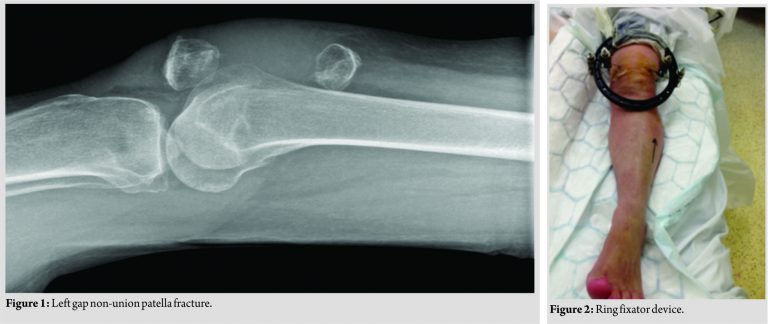

A 73-year-old fit and active female with a background of osteoporosis presented to our outpatient knee clinic following a fall from stairs after an original soft-tissue injury to the left knee 6 months prior. She reported progressive decline in mobility with difficulty extending the left knee. The patient did not want to seek medical attention and was referred by the general practitioner when her mobility became restricted to a wheelchair. On examination, the patient was dependent on a wheelchair. There was significant wasting of the quadriceps on the left. Her left knee range of movement was from 40° extensor lag to 90° flexion actively. Passive movements of the left knee were preserved. She was unable to straight leg raise (SLR). Plain radiographs of the left knee demonstrated a 12 cm gap non-union of the left patella (Fig. 1).

A decision was made to proceed with a two-staged reconstruction of the extensor mechanism. The first stage involved application of skeletal traction on the proximal fragment (Fig. 2 and 3). Due to the patient’s poor bone quality, the decision was made to apply tension wire skeletal traction using a ring fixator device with one wire passing through the bone and a second wire through the quadriceps tendon (Fig. 4). Following this, progressive traction was applied from 5 to 12 lbs over a period of 10 days. Once adequate mobilization of the proximal patella fragment was achieved, we proceeded to the second stage which involved a conventional tension band wiring to achieve definitive fixation (Fig. 4). At 1-year follow-up, the patient had achieved full independent mobility. She demonstrated full extension of the knee joint with preserved active SLR. She was subsequently discharged from follow-up.